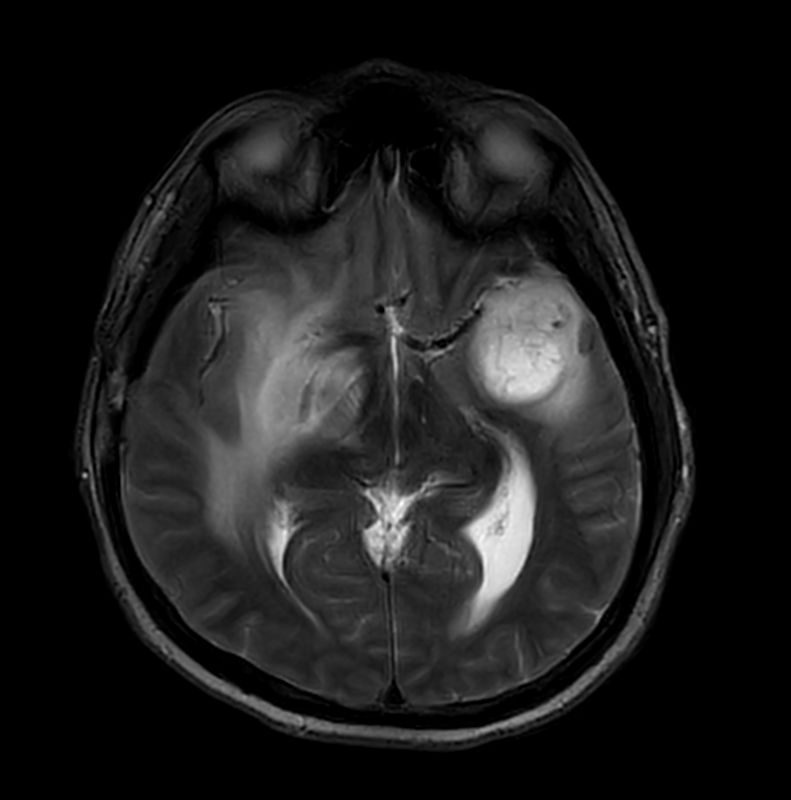

Large lesion brain imaging with synthetic MRI

Patient with a large brain lesion. AI based SmartSpeed is utlized to shorten scan time without compromise in image quality. Advanced imaging techniques like pCASL and 3D APT are used to perform contrast-free brain imaging to assess perfusion and tumoral activity. SWIp 3D susceptibility weighted offers the high sensitivity required to visualize deoxygenated (venous) blood or calcium deposits. A single synthetic (SyntAc) brain quantification scan is added. The resulting data of this scan can be used as input for advanced third party processing software* to synthesize MR images with different contrasts, brain parenchyma fraction maps and/or brain segmentation maps.

Axial T2w TSE Motion-Free